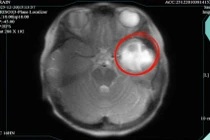

Từ khóa: Triệu chứng và dấu hiệu cảnh báo áp xe não